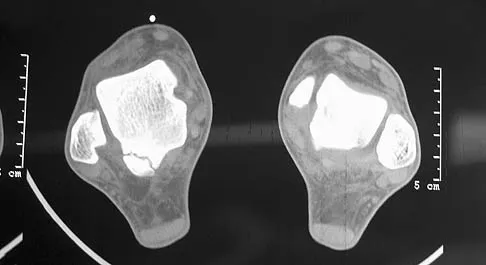

Question 63

In Figure 14, the primary fracture line in a calcaneal fracture is best depicted by which of the following schematics?